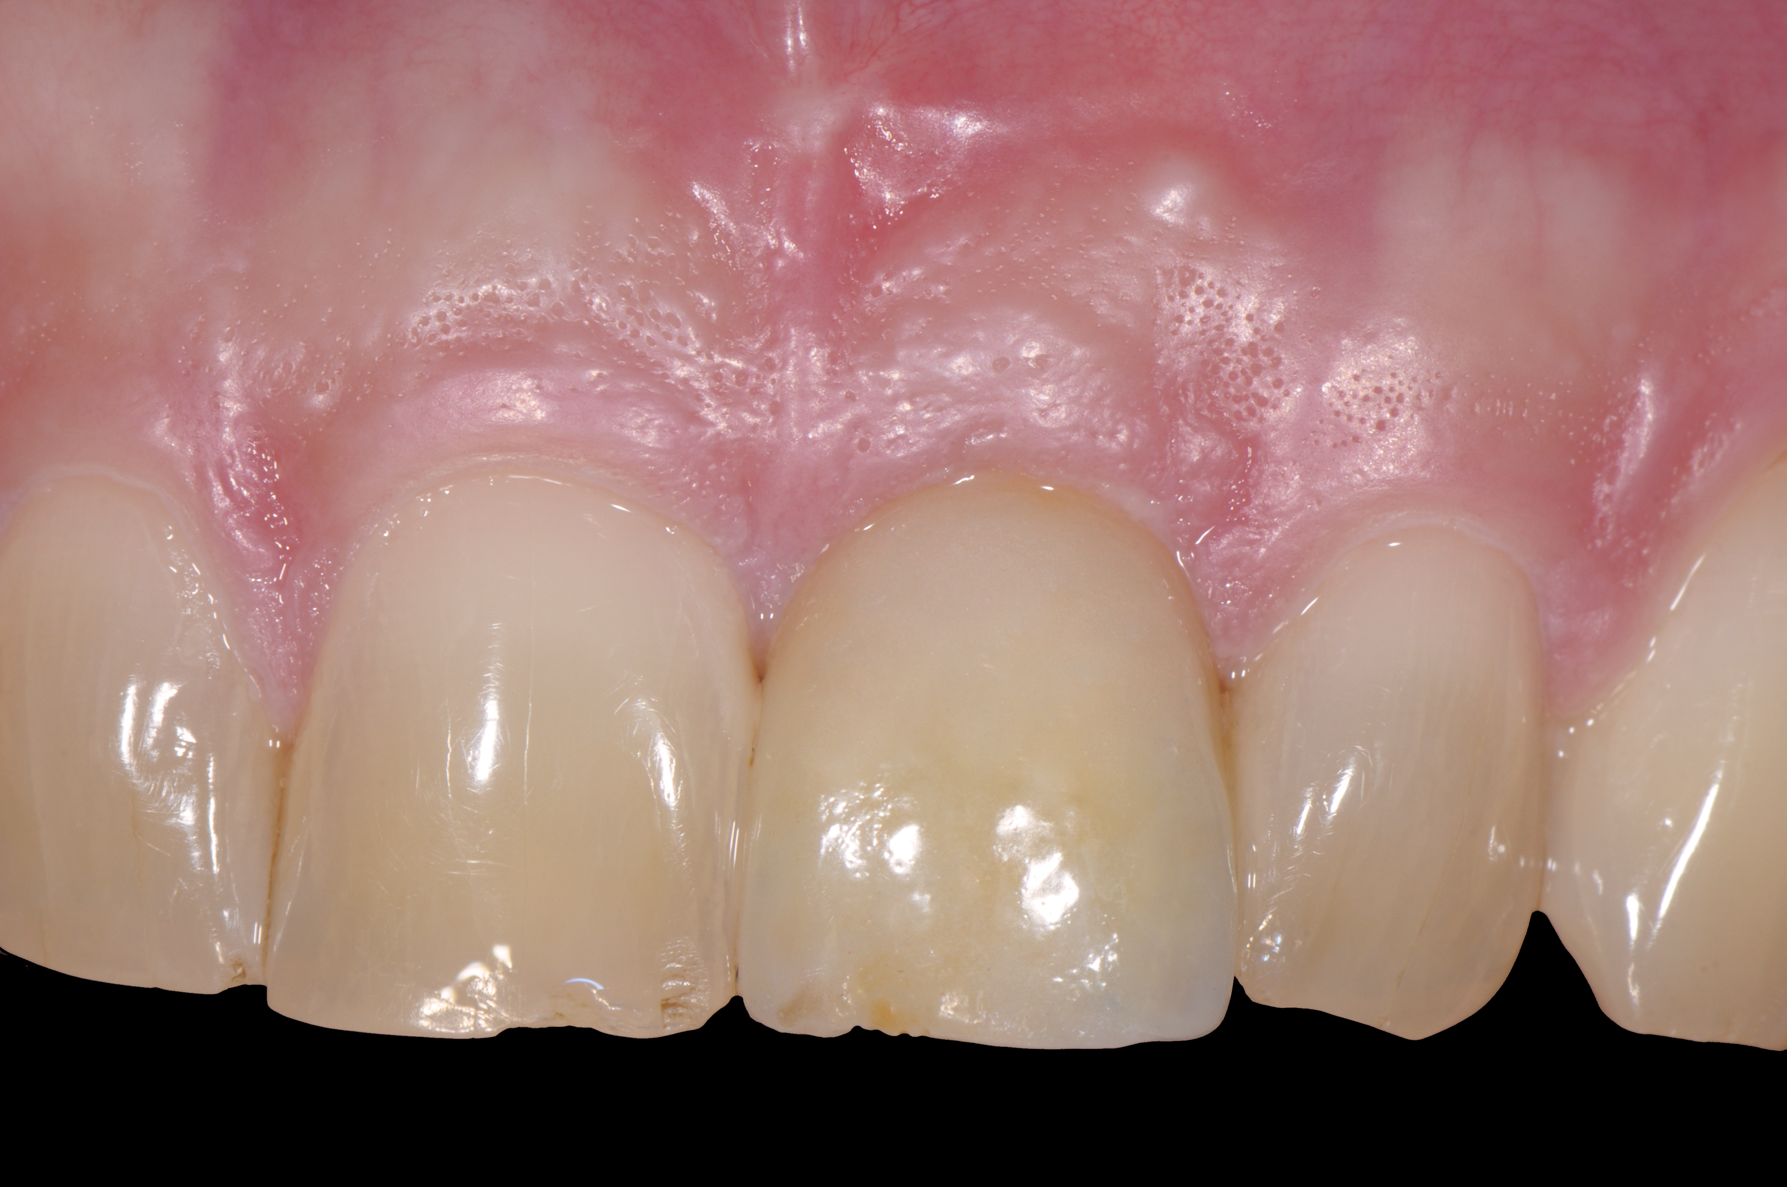

Fig 12. Metal-free, removable, screw-retained restoration. Peri-implant mucosa had no inflammation or discoloration.

Figure 12

Fig 14. Restoration at 3-year follow-up, showing stable and good esthetic tissue outcome.

Figure 14